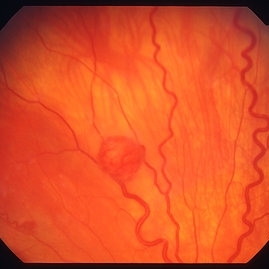

Retinal capillary hemangioma

Jan 11 2013 by Alex P. Hunyor, MD

Retinal capillary haemangioma nasal to optic disc, right eye.

Condition/keywords: retinal capillary hemangioma, Von Hippel-Lindau